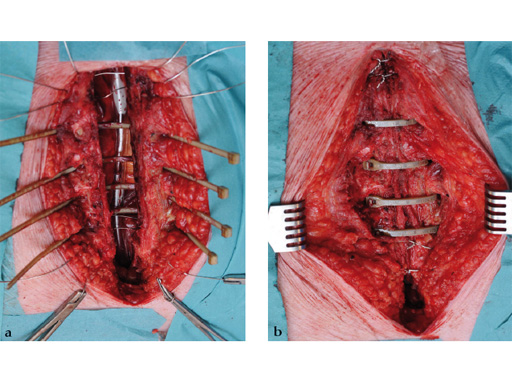

The sternal zipfix system primarily consists of polyetheretherketone (PEEK), biocompatible implants, which are similar to cable ties, and an application instrument. The purpose of this system is to achieve sternal closure following sternotomy by stabilizing the sternum and promoting fusion.

The implant itself comprises a removable stainless steel needle for peristernal application, the body with a ratchet mechanism, and a flat locking head. The application instrument is used to tension the implant, without overtensioning it, and also to cut it.

The patient was morbidly obese with a BMI of 45. Due to the high risk for sternal instability and/or deep sternal wound infection, closure was performed using the sternal zipfix system. The zipfix provides quick and reliable stable fixation of the sternum even in patients that are at a higher risk to develop a sternal instability or a deep sternal wound infection.